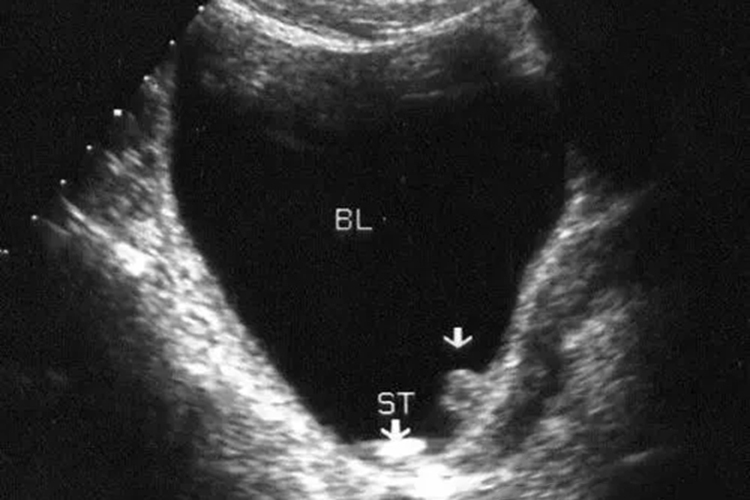

通常以下尿路刺激症状为主要临床表现,即尿频、尿急、尿痛,同时可伴有排尿困难、尿流中断现象,B超检查能发现膀胱及后尿道强光团及声影。